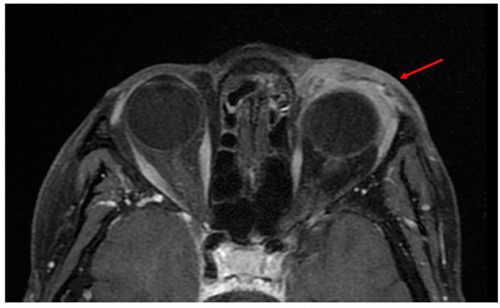

Three months later, an increased enophthalmos was noted. A magnetic resonance imaging (MRI) showed a thickening of the left upper and lower eyelids, up to the outer and inner canthus, infiltrating the glandular compartments and the lacrimal collectors without altering the intra or extraconic retro-septal fat. The infiltration was also observed in the superior, lateral and lower rectus muscles and the superior oblique muscle without any significant bone damage (Fig. 2). A biopsy of the left upper eyelid revealed infiltration of signet-ring cells and histiocyte-like cells. An extensive clinical workup, including whole-body positron emission tomography using fluorodeoxyglucose (FDG), did not identify any lesion in the left periocular region nor any extra-ocular FDG-avid lesions. A breast MRI was also performed to exclude a primitive breast carcinoma, while an oeso-gastro-duodenoscopy and colonoscopy did not show any sign of primary tumor or metastases.

MRI showing a thickening of the left preorbital soft part (arrow), infiltrating the glandular compartments and lacrimal collectors with no alteration of intra or extraconic retro-septal fat.